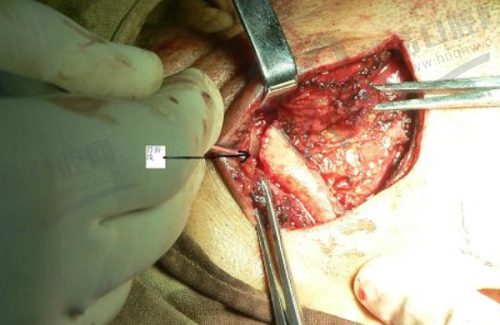

周毅医生在种植牙领域有着极高的造诣。他是口腔种植和口腔修复两个首批国内临床重点专科的骨干成员,在医院先开展了穿颧种植等一系列高难度手术和治疗项目,折断种植体螺丝取出技术处于国内外领跑地位。

近年来,他筹建了武汉大学口腔医院光谷院区口腔种植和修复中 心,并带领该中 心获得了2024年医院标兵科室荣誉称号,还参与建立了医院第一个多学科诊疗门诊。在学术研究方面,他成果斐然,在种植体周组织反应机制、数字化种植修复精度优化等研究中取得突破,发表SCI论文32篇,实现获国内专项9项,参与起草4项国内团标。